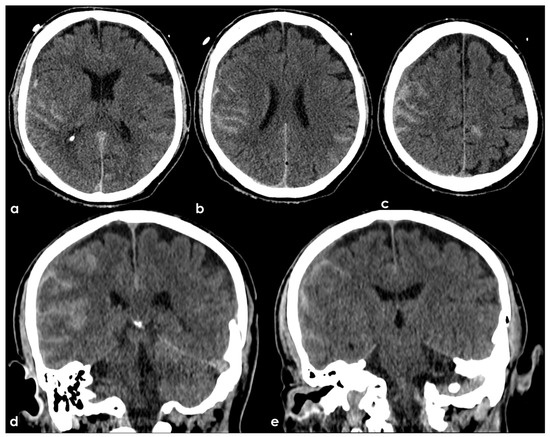

7. Structural Neuroimaging Markers